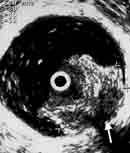

Эндовезикальное сканирование позволяет дифференцировать все слои мочевого пузыря (Рис. 1). Между мышечной стенкой и слизистой оболочкой визуализируется гипоэхогенная подслизистая соединительная ткань. При стадии рака мочевого пузыря Та (инвазия в пределах слизистой) создается впечатление, что опухоль отделена от мышечной стенки мочевого пузыря, то есть подслизистый слой остается неизмененным (Рис. 2), также хорошо визуализируются устья мочеточников. При распространении инвазии субэпителиальной соединительной ткани (стадия Т1) опухоль уже непосредственно прилежит к мышечному слою, но не инвазирует последний (Рис. 3).

Рис. 2. Цистэндосонограмма. Рак мочевого пузыря стадия Та.

1 - опухоль,

2 - устья мочеточников.